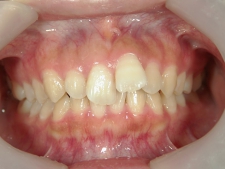

アクアシステム(透明マウスピース矯正)/上顎のみ 症例(14)

25歳 女性 磐田市在住 治療期間2年

矯正歯科 治療前矯正歯科 治療前

矯正歯科 治療前 正面